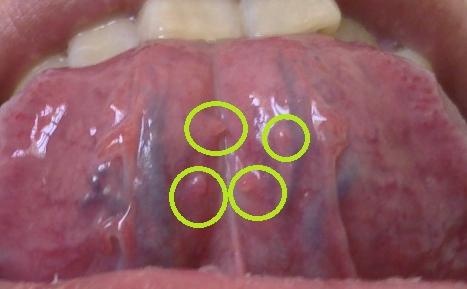

口腔尖锐湿疣图片是什么样子呢